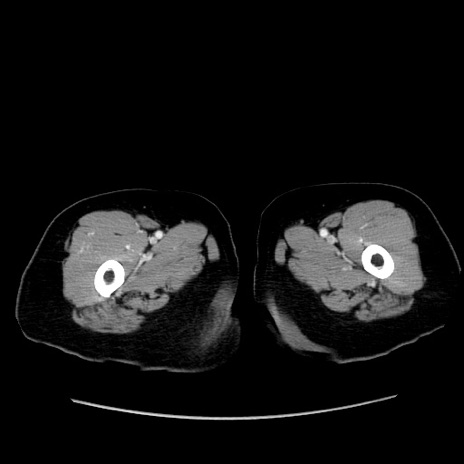

症例19(横断像)

【症例】80歳代女性

【主訴】下腹部痛

【現病歴】約8時間前より下腹部痛の出現あり、救急外来受診。

【既往歴】両側付属器切除

【身体所見】意識清明、下腹部正中に手術痕あり、その部位に一致して圧痛と反跳痛あり。腸蠕動音は亢進。

【データ】WBC 9300、CRP 0.15